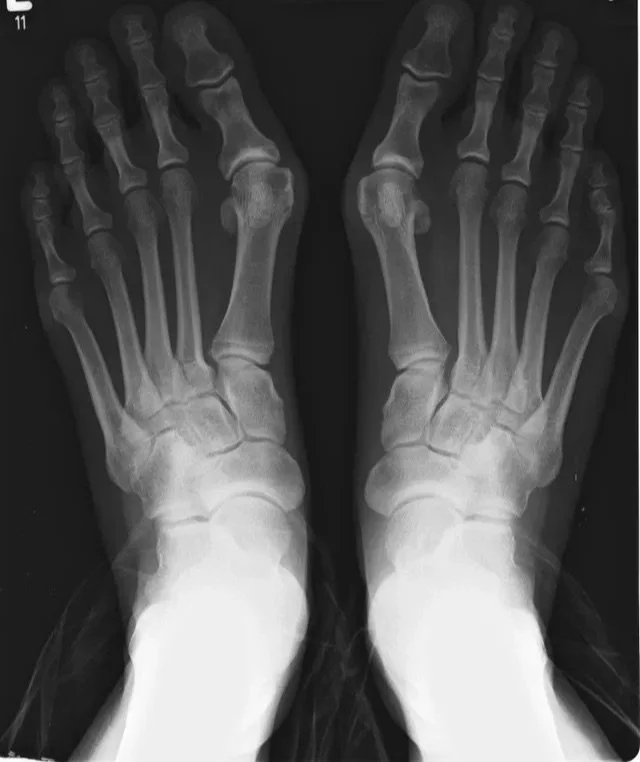

Bunion (hallux valgus)

A bunion, also known as hallux valgus, is a progressive deformity of the big toe joint in which the toe drifts toward the smaller toes, creating a painful bony prominence along the inside of the foot. Over time, bunions can lead to joint degeneration, altered gait mechanics, and difficulty with footwear.

Diagnosis of a bunion begins with a thorough clinical examination, including evaluation of toe alignment, joint motion, areas of tenderness, and overall foot mechanics. Gait assessment is often helpful in identifying abnormal loading patterns.

Weight-bearing X-rays are used to confirm the diagnosis and assess the severity of the deformity. Imaging allows for evaluation of joint congruency, angular alignment, and the presence of arthritis, all of which are important for guiding treatment decisions.